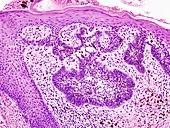

Retina (part of the eye) stained with hematoxylin and eosin, cell nuclei stained blue-purple and extracellular material stained pink.

H&E is the combination of two histological stains: hematoxylin and eosin. The hematoxylin stains cell nuclei blue, and eosin stains the extracellular matrix and cytoplasm pink, with other structures taking on different shades, hues, and combinations of these colors.[5][6] The stain shows the general layout and distribution of cells and provides a general overview of a tissue sample's structure.[7] Hence a pathologist can easily differentiate between the nuclear and cytoplasmic parts of a cell.

Hematoxylin principally colors the nuclei of cells blue or dark-purple,[6][15][14] along with a few other tissues, such as keratohyalin granules and calcified material. Eosin stains the cytoplasm and some other structures including extracellular matrix such as collagen[5][7][14] in up to five shades of pink.[8] The eosinophilic (substances that are stained by eosin)[5] structures are generally composed of intracellular or extracellular proteins. The Lewy bodies and Mallory bodies are examples of eosinophilic structures. Most of the cytoplasm is eosinophilic and is rendered pink.[10][15] Red blood cells are stained intensely red.